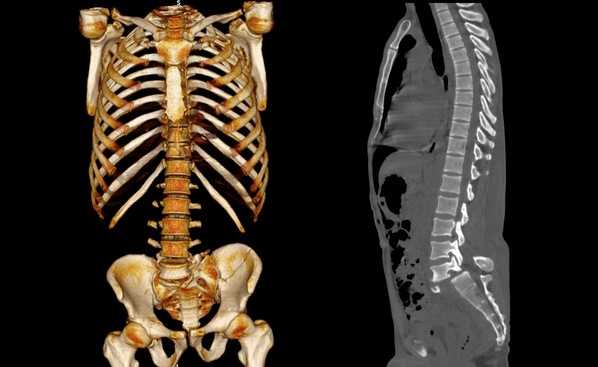

КТ позвоночника что показывает

Компьютерная томография является одним из наиболее популярных видов изучения костных и хрящевых анатомических образований. Сканирование проводят с помощью рентгеновского излучения. Твердые ткани организма активно поглощают ионизирующие потоки, обеспечивая возможность детальной визуализации строения внутренних структур. КТ позвоночника проводят для определения состояния костных и хрящевых элементов, окружающих тканей, кровеносных сосудов.

В результате компьютерной томографии получают серию послойных изображений рассматриваемой зоны. Монохромные фотографии обладают высоким разрешением. В отличие от рентгенографии на снимках отсутствуют дефекты и тени от расположенных рядом структур. Изменение плоскости при реконструкции изображений позволяет тщательно изучить анатомические образования. Преимуществом КТ является возможность создания 3D-модели позвоночника.

Компьютерная томография позвоночника показывает малейшие нарушения строения и функциональности суставных элементов. Трехмерное изображение при подготовке к хирургическому вмешательству позволяет локализовать патологический процесс, уточнить объем предстоящей операции.

Трехмерная реконструкция при КТ

Компьютерная томография позвоночника